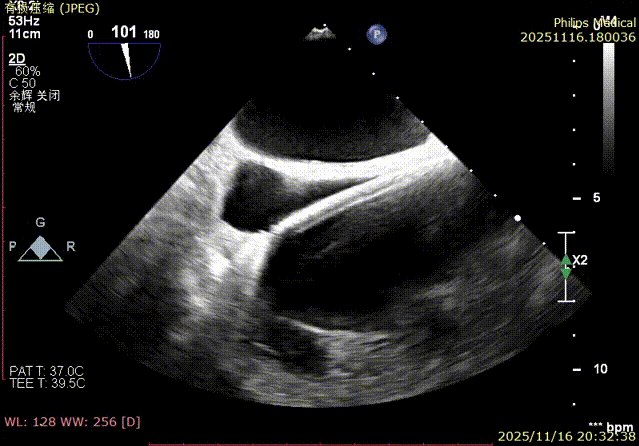

K-Clip® Tricuspid Annuloplasty (Seamless Transition):Immediately after LAAC, the operators established a new vascular access route and advanced the K-Clip® delivery system directly into the right atrium, targeting the posterior-septal and anterior-posterior commissures of the tricuspid annulus. Under real-time ultrasound guidance, the team precisely anchored, clipped, and released the devices.

Immediate intraoperative echocardiographic verification showed that the tricuspid regurgitation area was significantly reduced from a preoperative grade of 5+(pre-op) to 2+(post-op), downgrading the severity from extreme to mild-moderate.

- TR Severity Comparison: Reduced from 5+ to 2+.

- Annulus Area Reduction: Decreased by 50%.

- Immediate Overall Verification: At the conclusion of the surgery,复查 (re-examination) via TEE confirmed no residual shunt or pericardial effusion around the LAA occluder, and the tricuspid valve repair results were satisfactory. The patient remained hemodynamically stable, marking the complete success of the one-stop procedure.